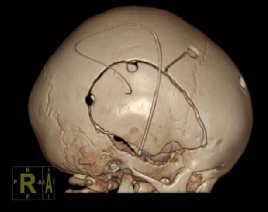

9月,凯凯被送入手术室。在先进的神经导航系统和术中监护技术的辅助下,手术团队开始了精细操作。医生们精准地铣开双侧已骨性融合的颞鳞缝,小心游离骨瓣并进行减张固定,同时松解了紧张的冠状缝。整个手术过程犹如一次精密的“颅骨雕塑”,在微创理念指导下,操作精准无误,未对脑组织造成任何损伤,成功实现了颅腔容积的有效扩大。

术后